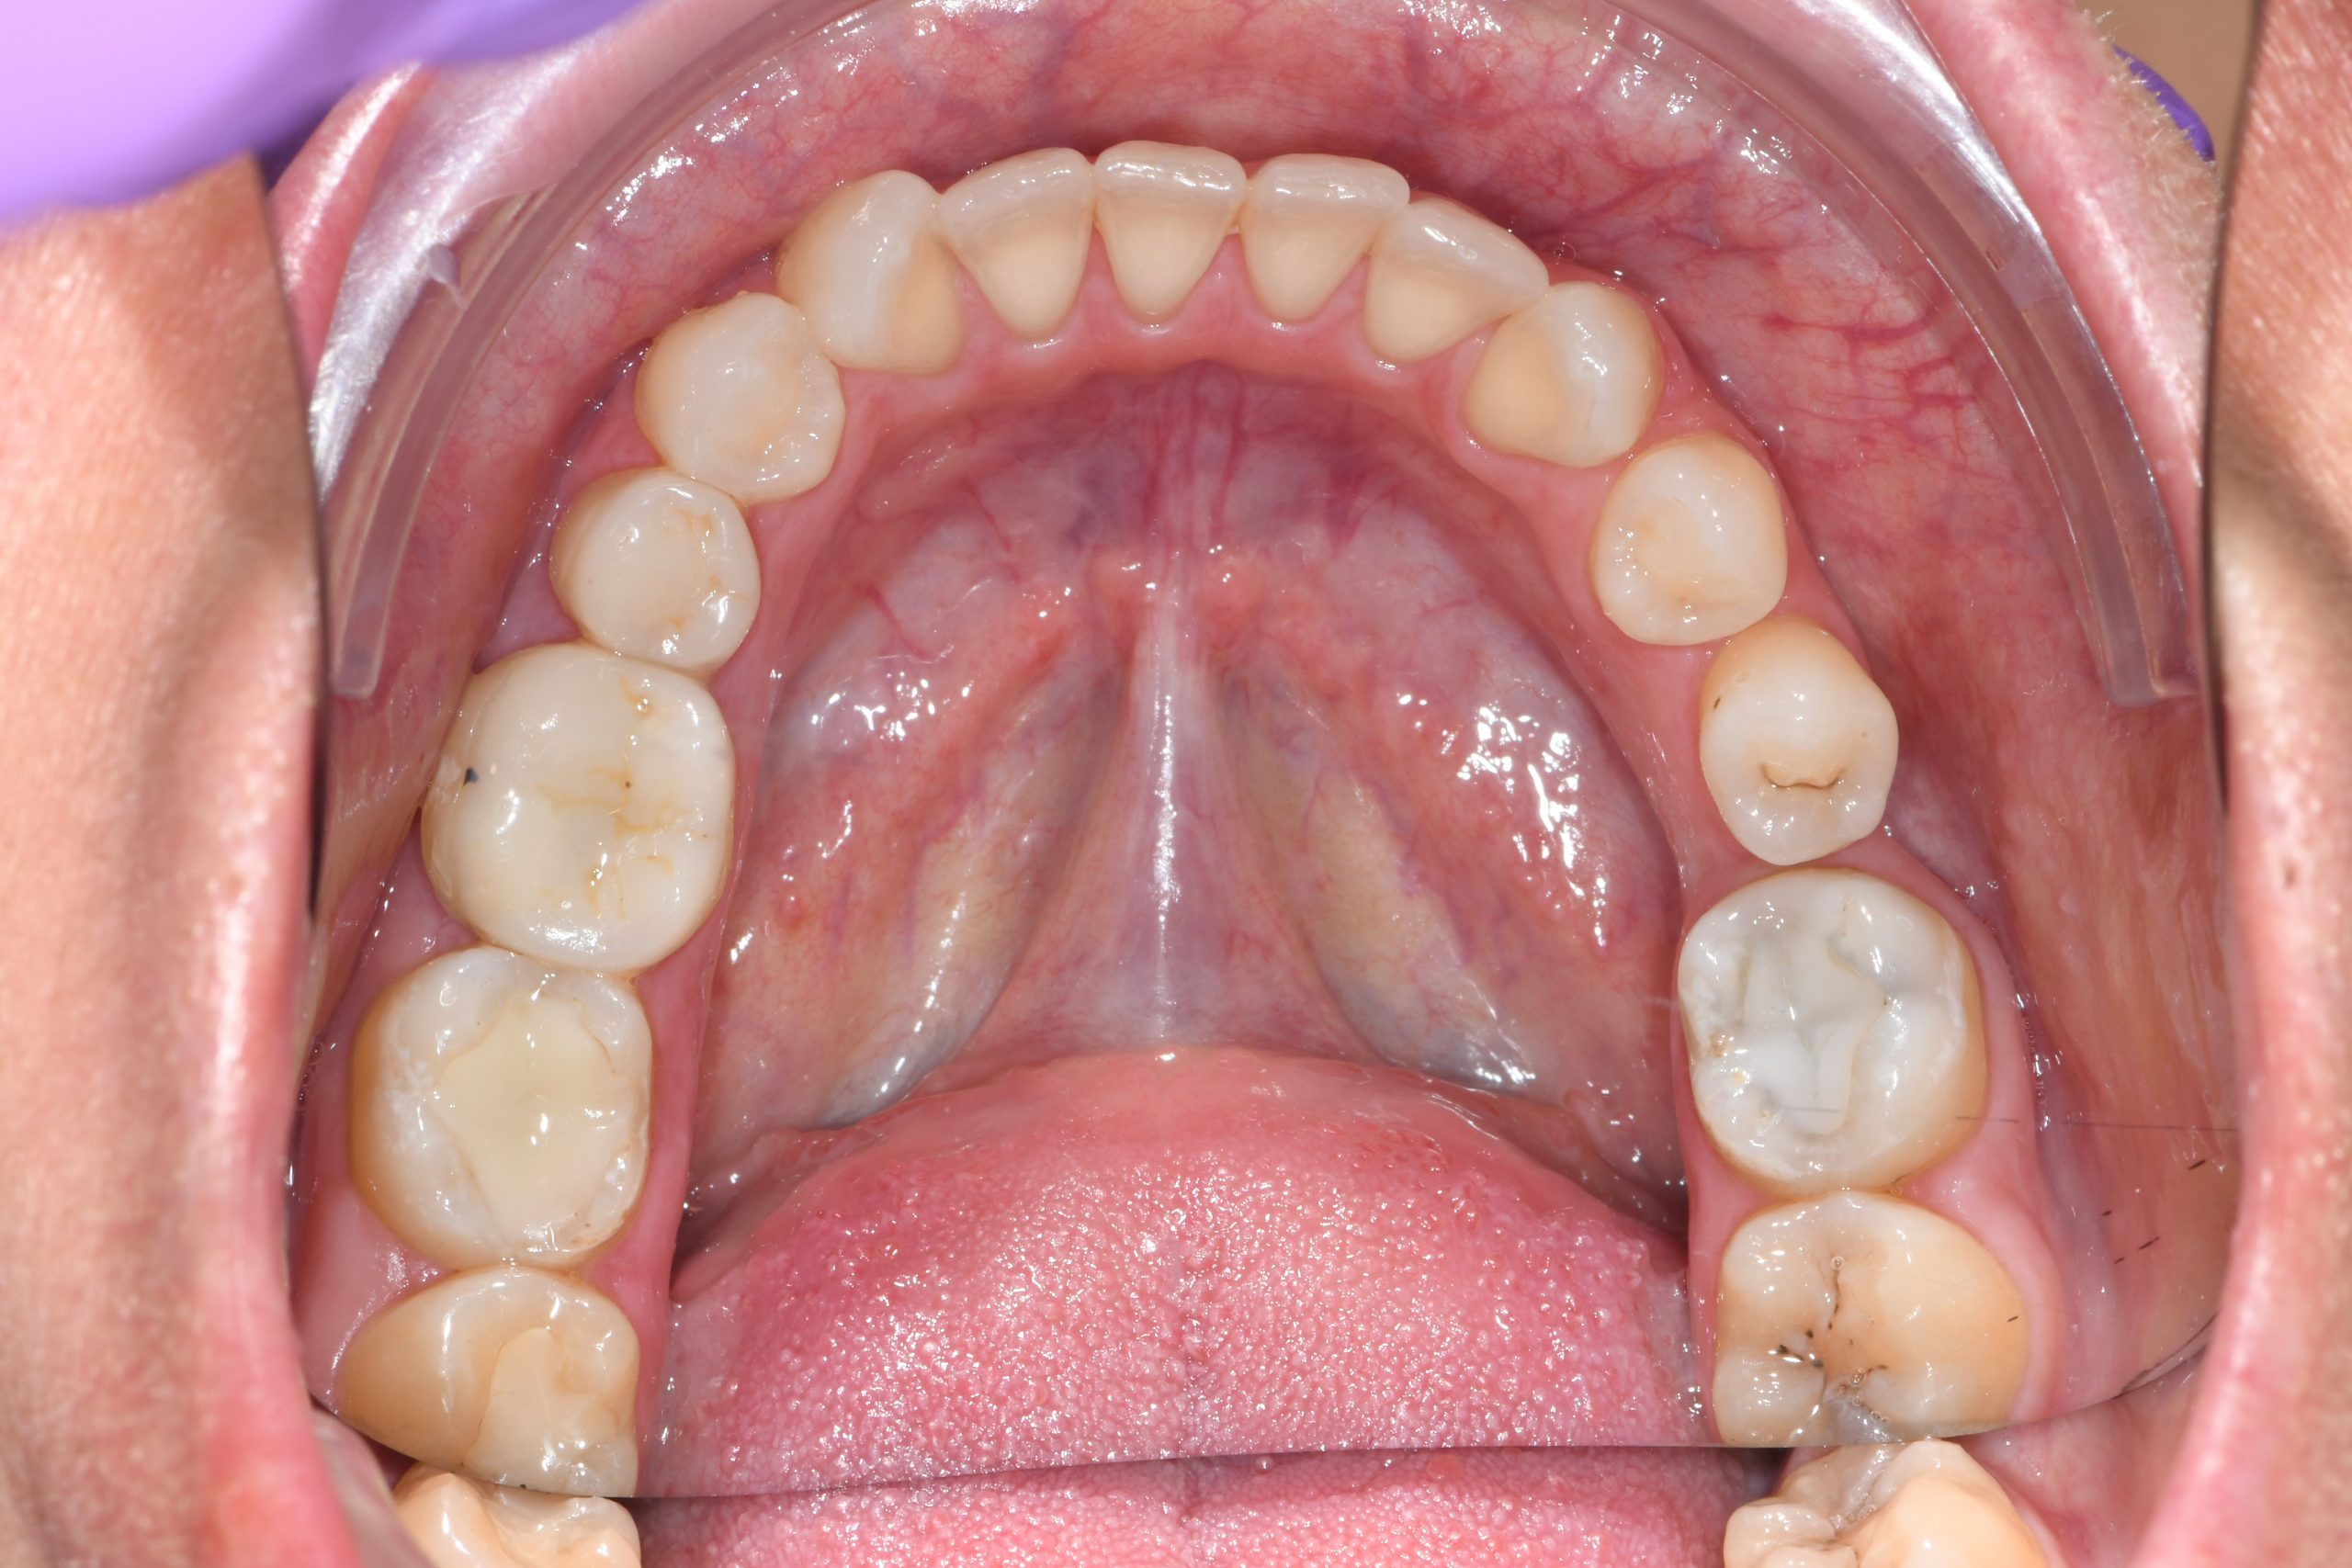

Az elmúlt évekből rengeteg szakmai referenciát tudnánk bemutatni, amelyek különböző fogszabályozási problémákat oldottak meg. Válogatva a több száz esetből, ezen az oldalon olyan képeket, információkat igyekeztünk bemutatni, amelyeknek a segítségével a jövőbeni pácienseinknek azt tudjuk üzenni: A Te fogsorod is lehet gyönyörű!

(Képeket a Pácienseink külön írásos beleegyezésével mutatjuk be!)